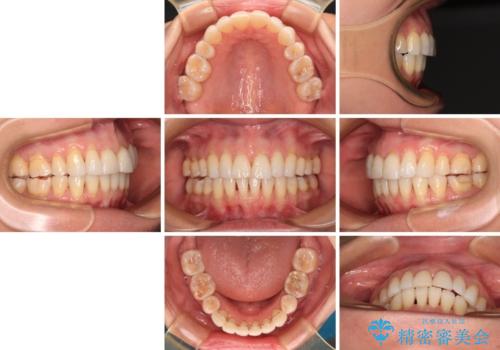

- 上の前歯の出っ歯を治したいとのことで来院された患者様です。

後戻りによる再矯正というもともあり、インビザラインを希望されていました。

上顎の歯は後方移動とIPR(歯と歯の間を削る)によって口元が引っ込むように、下顎は歯列全体の拡大とIPRによって上顎とバランスよく咬み合うように設計し、インビザラインにより治療を行うこととしました。

治療を開始して暫くして、勤務先から2年以上帰国することができず、それまでの移動がほとんど後戻りしてしまい、帰国後に再度後戻りをリカバリーするための治療を行うこととなりました。

5年以上の治療期間がかかりましたが、気になっている部分を改善することができました。